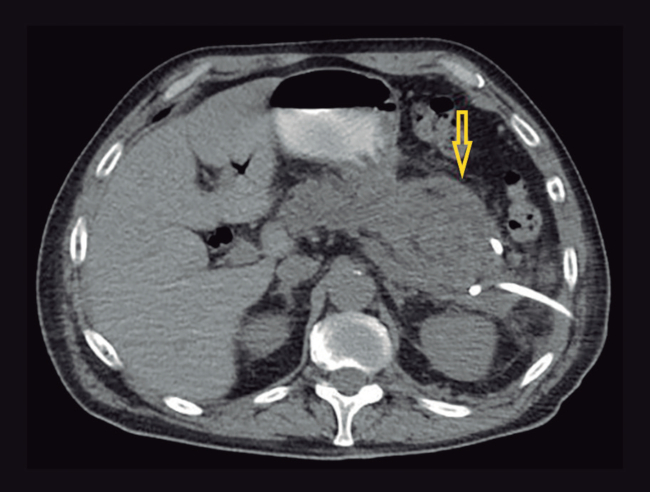

Se realiza papilectomía endoscópica y se presenta como complicación una pancreatitis aguda severa necrotizante. A las cuatro semanas, el paciente evoluciona febril, con tomografía computada que evidencia un marcado aumento difuso del volumen y el tamaño del páncreas, asociado a múltiples colecciones heterogéneas, con pared definida amurallada con componente mixto a predominio líquido, imágenes aéreas en su interior localizadas en la región peripancreática, predominando dos colecciones definidas en cuerpo y cola (69 x 50 mm y 77 x 54 mm), con extensión a espacio perirrenal, raíz del mesenterio y ambas goteras parietocólicas, sin realce tras la administración de contraste, lo que sugiere necrosis (Figura 1). Debido a la naturaleza predominantemente líquida de las colecciones, se colocan inicialmente dos drenajes percutáneos guiados por tomografía hacia colección de cuerpo y cola, con lavajes diarios con solución fisiológica. Se aísla por cultivo Acinetobacter baumanii. El paciente evoluciona tórpidamente, manteniéndose febril de manera persistente y se agrega falla multiorgánica. En control tomográfico se observa una franca disminución de colección de localización cefálica con persistencia en cola de páncreas en el espacio perirrenal y en espacio gastropancreático, sin contacto con la pared gástrica (Figura 2). Por persistencia de walled-off necrosis en cola de páncreas, ausencia de contacto con pared gástrica o duodenal, y sin contar en la institución con endosonografía sumado a mala respuesta clínica, se decide el abordaje endoscópico transcutáneo con colocación de stent metálico esofágico autoexpandible parcialmente cubierto.